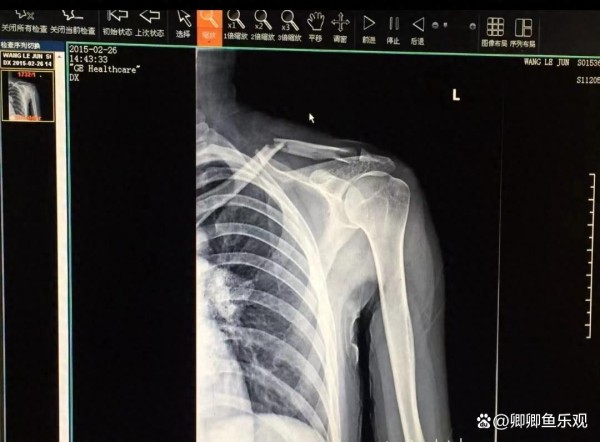

王乐君对此回应非常坦诚,她乐意解开这个谜团,希望通过分享自己的经历,帮助那些同样遭遇锁骨骨折的人。她展示了一张X光照片,照片上清晰可见,王乐君的锁骨已完全断裂。她表示,当时是因为胡歌意外压到她,导致这次骨折。

接下来,她详细描述了自己的伤势以及治疗过程。因为伤势较重,她在医生的建议下选择了手术治疗,手术中在她身体内放置了七颗钢钉。不过手术后的恢复期并不是一帆风顺,由于工作的特殊性,王乐君并没能得到充分休息,钢板出现了问题,不得已又要吃止痛片继续拍摄。